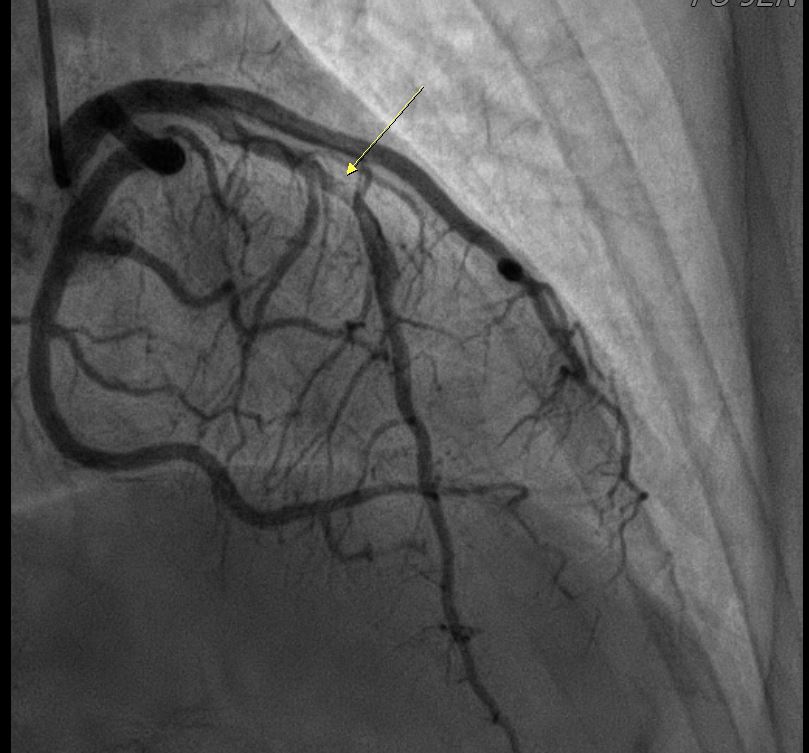

In the STEMI episode, in Dec, 2022, the LCX and RCA were patent. There were multiple odd stenotic lesions with in mid LAD, with some haziness suggested limited contrast filing. Six days after PCI, there was dissection flap, extending beyond previous angioplasty, with limited flow in LAD, compatible with the unstable ECG changes. In the NSTEMI episode, in Dec, 2022, the LAD was stationary without restenosis. But the RCA for new log lesion at segment 2 to segment 3.

1st PCI for STEMI 1. The odd LAD lesion was checked by IVUS,revealing coronary dissection in mid LAD. 2. Angioplasty was performed with a 2.75*10mm Wolverine cutting balloon up to 8A10¡±, with fair LAD flow. --2nd PCI for recheck and unstable ECG findings 1. For dissection flap extending to distal LAD, wiring with a Sion wire was performed carefully. 2. Check IVUS to confirm true-lumen wiring and the extension of the dissection. Intimal flap and large burden of sub-intimal hematoma were noted. 3. Angioplasty with a 2.0*20mm balloon catheter, but with poor distal flow. 4. Long stenting to mid-to-distal LAD according to IVUS findings, with Onyx 2.0*26mm and Onyx 2.5*30mm 5. Angioplasty with a 1.5*20mm balloon catheter for distal run-off, 4A10¡± 6. Post-stenting dilatation with a 2.5*10mm balloon catheter, 4A10", low pressure considering the sub-intimal hematoma 7. Check final IVUS: The stents were well apposed. The proximal sub-intimal hematoma was not fully covered due to the vessel-size discrepancy. 8. The final flow was fair --3rd PCI for NSTEMI 1. For the un-reasonable rapid progression of the RCA lesion, I checked IVUS and coronary dissection was noted again. 2. No PCI was performed thereafter due to acceptable blood flow. --4th cath half years later The LAD was stationary and the RCA lesion was totally resolved.